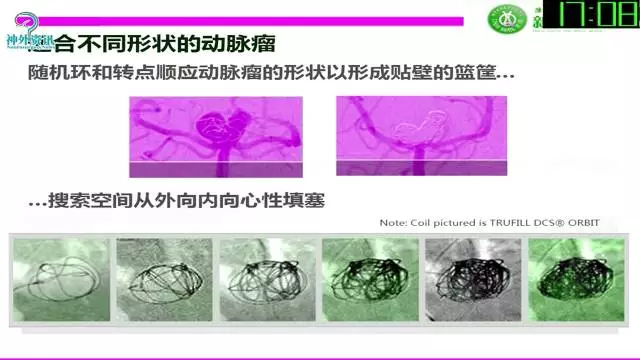

今天为大家分享的是“强生医疗CNV-神经介入专栏”第三十六期,由重庆第三军医大学附属新桥医院神经外科刘俊带来的“Galaxy弹簧圈在不规则动脉瘤中的临床应用”精彩讲课视频及PPT,欢迎观看。文章仅代表作者个人观点,如有不同见解,欢迎同道斧正!